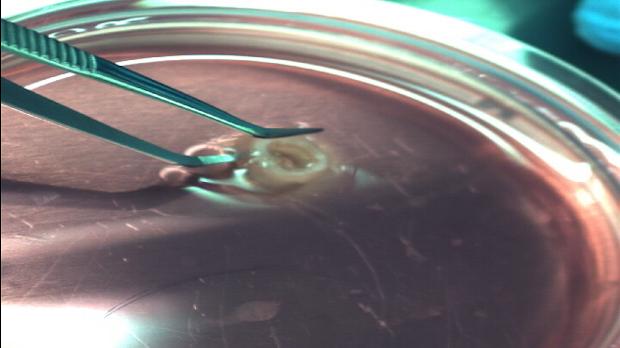

Sabanc� �niversitesi, d�nyada bir ilk olarak 3B biyo-yaz�c� ile canl� h�creler kullanarak aort damar� doku yap�s�n� �retmeyi ba�ard�...

Ekip, �al��mas�n� �niversiteye ba�l� Nanoteknoloji Uygulama ve Ara�t�rma Merkezi�nde ger�ekle�tirdi. Proje ekibinin ba��ndaki isim olan Do�. Dr. Ko�, daha �nce yap�lm�� doku m�hendisli�i �al��malar�ndan farkl� olarak kendilerinin �� boyutlu bas�mda canl� h�creleri biyo m�rekkep olarak kulland�klar�n� s�yledi.

H�creleri el de�dirmeden bast�klar�n� anlatan Ko�, �Dokunun 3 boyutlu anatomisini belirledikten sonra biyoyaz�c�y� kontrol etmek i�in komutlar� dosyaya kaydediyoruz. Daha sonra bu komutlar� kullanarak biyo-yaz�c�n�n nereye h�cre nereye destek yap�s� basaca��n� kontrol ediyoruz. Projede fonksiyonel organ veya doku yapam�yoruz ama birebir organ�n bir par�as�n�, geli�tirdi�imiz programlarla tasarl�yoruz� dedi.

Ko�, gelece�e d�n�k planlar�n� da ��yle anlatt�: ��leriye d�n�k en �nemli hedef, 3B Biyo-yaz�c� ile hastan�n kendi normal h�crelerini kullanarak, gereken doku hatta organ�n�n birebir kopyas�n� �retebilmek. B�ylece, hastan�n kendi h�creleri ile �retilen yapay organ� hastan�n v�cudunun reddetmesi gibi bir durum olmayacak.�